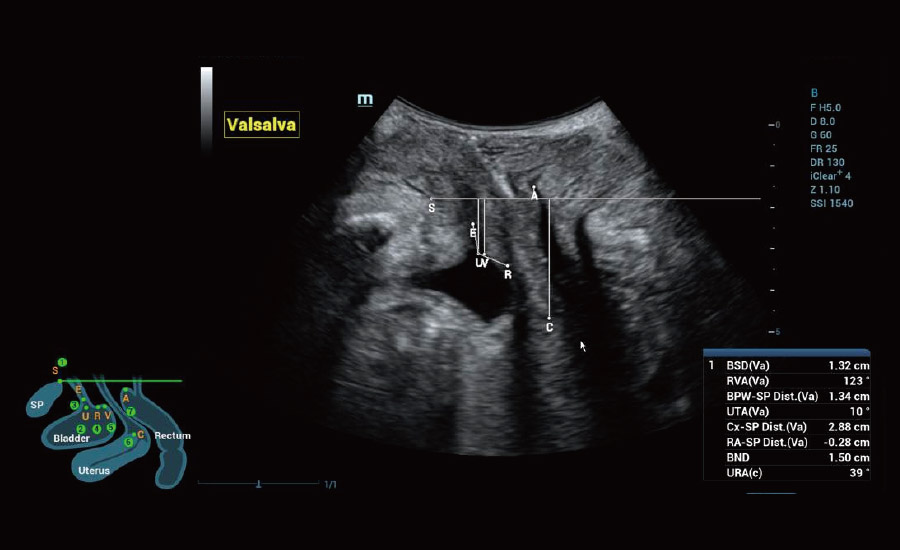

Informa??es abrangentes adaptadas aos cenƔrios

Por meio da combina??o de algoritmos avan?ados e do conhecimento especĆfico da regi?o, a inovadora solu??o Smart Scene permite a identifica??o automĆ”tica das caracterĆsticas do tecido e fornece diagnĆ³stico especĆfico dos Ć³rg?os com informa??es completas. Com base na identifica??o automĆ”tica de cenĆ”rios, a solu??o realiza n?o apenas a varredura 2D inteligente com configura??es e medidas automĆ”ticas, mas tambĆ©m oferece informa??es 3D abrangentes em todas as etapas, desde a otimiza??o de imagens volumĆ©tricas atĆ© a difĆcil obten??o de planos 2D, e a quantifica??o durante todo o procedimento. Ele ajuda a reduzir em grande parte a dependĆŖncia de habilidades clĆnicas, ao mesmo tempo que aumenta a precis?o, a confian?a e a eficiĆŖncia no diagnĆ³stico.

- Cuidando da saĆŗde da mulher com solu??es em ginecologia e uroginecologia

Uroginecologia